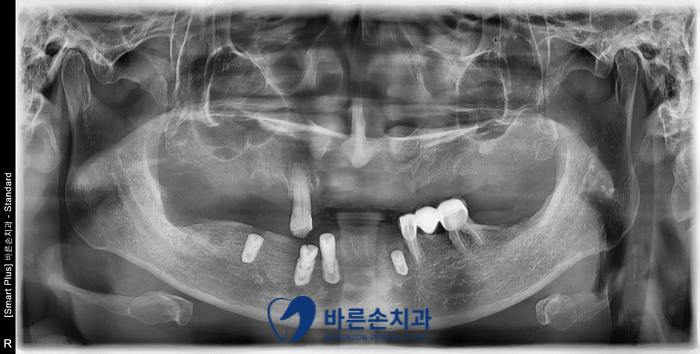

먼저 치아 상태와 치조골(뼈) 상태를 확인하기 위해서

파노라마, CT촬영을 시행했습니다.

파노라마 사진을 확인해보니 치아를 잡아주는 치조골이 많이 내려가있네요..

치조골이 많이 상실되어 치아가 둥둥 떠있는 형상입니다.